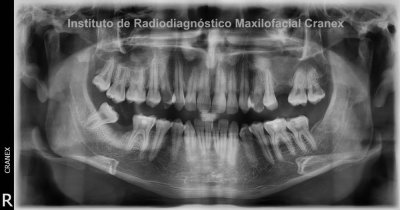

A la evaluación de las radiografías Panorámica, Waters, y radiografía Periapical, observamos, neumatización alveolar y opacificación parcial de seno maxilar izquierdo, lecho alveolar de correspondiente a pieza 2.6, con discontinuidad de la cortical de la pared basal de seno maxilar adyacente, y engrosamiento de la membrana antral de seno maxilar ipsilateral. Signos radiográficos compatibles con proceso inflamatorio sinusal (Sinusitis) en relación a comunicación buco sinusal.